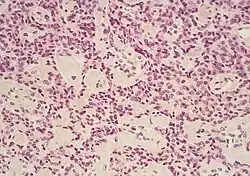

Micrograph of pancreatic ductal adenocarcinoma (the most common type of pancreatic cancer), H&E stain

Micrographs of normal pancreas, pancreatic intraepithelial neoplasia (precursors to pancreatic carcinoma) and pancreatic carcinoma, H&E stain